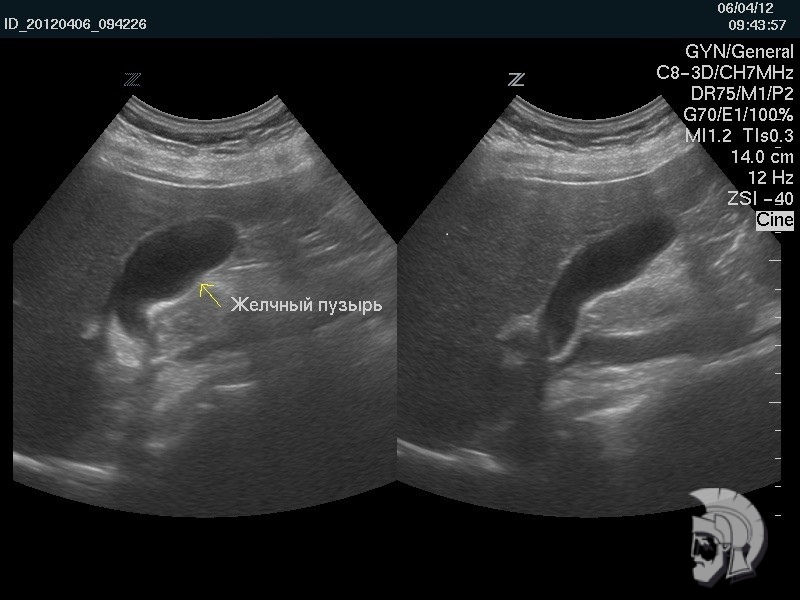

| 3D-фото желчного пузыря. Тот же случай |

Фото желчного пузыря.

Исследование функциональной активности желчного пузыря у мужчины 35 лет: желчный пузырь правильной формы в начале исследования (слева) и после частичного опорожнения (справа) |